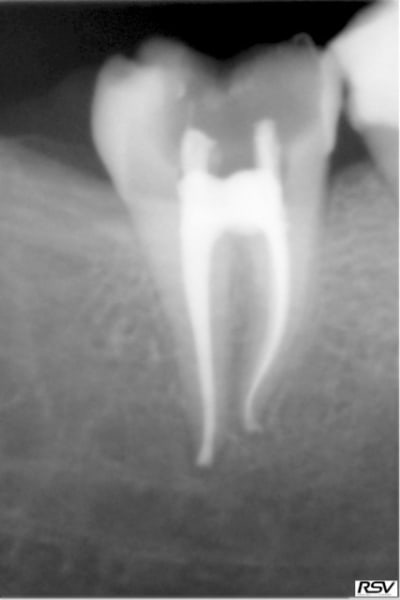

pffff...vi bin deux secondes ! :):) quand ce sera fini ça n'aura pas grand intéret , juste j'ancrerai pour repartir les contraintes différemment)

bien sur le canal est repris, mais juste parce que j'ai dû y retourner pour déposer ce maudit truc si bien collé,et je ne vais pas dans les canaux mesiaux

largement? tenon passif noyé dans matrice collée, un plaisir c'est sur:)

sorry, fallait trouver la rd (heu...cherche pas suis au bout:):) )

Joli , ton retraitement, n'athos! (tu as contourné la ferraille coincée avec maestria!)

merci mon nadhoc! mais c'était pas de la feraille , c'est cette nouvelle mode du tenon plastoc non ajusté au canal (ou plus exactement sous ajusté) et noyé dans une résine collée aux parois (je crois qu'il y a eu un article récemment dans l'ID)

le but étant de réduire, ou plûtot de répartir astucieusement les contraintes en caressant les coef d'élasticité dentine, resine, pivot etc...parce qu'on veut éviter qu'un pivot metal, ajusté au canal, n'amorce felures et fractures

alors on voudriat coller (tiens! un bouble-sens!) aux résistances naturelles de la structure dentaire.

Moralité, comme naturellement les contraintes s'accumulent au tiers cervical, bin c'est là que ça a cassé...c'était du trop good job! :)